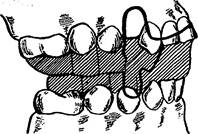

Скользящую дугу Энгля применяют при наличии протрузии передних зубов и трем между ними. С помощью этого аппарата можно провести уплощение переднего участка верхнего зубного ряда. Дуга представляет собой отрезок стальной нержавеющей проволоки, концы которой свободно перемещаются в трубках, что связано с отсутствием гаек. Действующей силой являются резиновые кольца. К дуге припаяны зацепные крючки. Между зацепными крючками, припаянными к дуге на уровне первых премоляров, и трубками справа и слева натянуты резиновые кольца. Чтобы дуга не соскальзывала, к десне в переднем отделе припаивают ленточные перекидные кламмеры (рис. 13.44).

Дуги Энгля можно использовать для наложения межчелюстной резиновой тяги между зубными ряда-

Рис. 13.44. Скользящая дуга Энгля.

ми. Ее применяют для смещения нижней челюсти вперед или назад. Одновременно зубной ряд и альвеолярный отросток верхней челюсти испытывают нагрузку в противоположных направлениях (рис. 13.45).

Рис. 13.45. Межчелюстная косая резиновая тяга (слева) для исправления сагиттальной резцовой дизокклюзии и обратной резцовой дизокклюзии (справа).